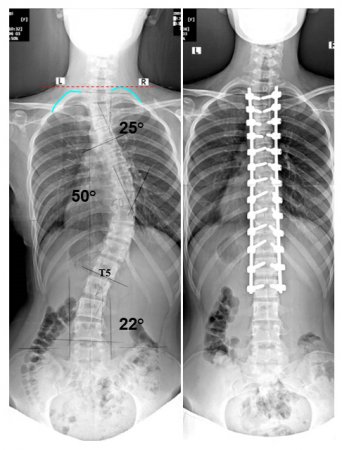

Omurga operasyonlarında gelişebilecek sorunlar

Omurga operasyonları zor ve tecrübe gerektiren operasyonlardır. Omurga operasyonları riskli ameliyatlardır. Bu riskler yapılacak omurga

sorununa ve genişliğine göre farklılıklar göstermektedir. Yapılacak omurga segment sayısı arttıkça çıkabilecek sorunlar artmaktadır.

Skolyoz ve kifoz cerrahisinde riskler daha fazla ve çıkabilecek komplikasyonlar çok daha fazladır.Bu gelişebilecek erken veya geç

Omurgada kaymalar olabilir, omurgada kırıklar olabilir, omurgada eğrilikler kifoz veya skolyoz olabilir. İşte bu sorunlar derecelerine tespit